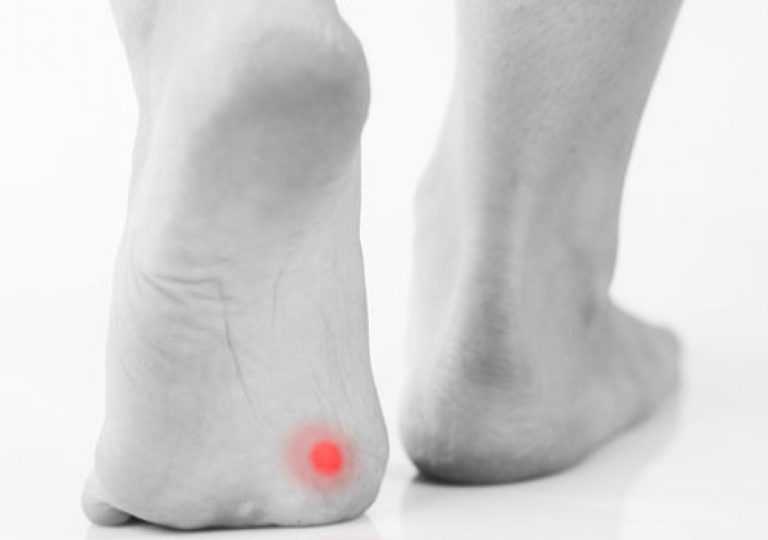

Οι ρόζοι και οι κάλοι στα πόδια είναι ενοχλητικοί και συχνά επώδυνοι χόνδροι, που σχηματίζονται στο δέρμα σε σημεία αυξημένης πίεσης, ή/και τριβής. Ο ιατρικός όρος για αυτήν την πάχυνση του δέρματος είναι υπερκεράτωση.

Οι κάλοι στα πόδια περιγράφουν μια πιο διάχυτη, αλλά και πιο επίπεδη πάχυνση του δέρματος, ενώ οι ρόζοι περιγράφουν μια πιο σκληρή πάχυνση, όπου το δέρμα ανασηκώνεται και σχηματίζει ένα κωνικό, ή κυκλικό σχήμα.

Οι κάλοι στα πόδια εμφανίζονται κατά κανόνα στο εξωτερικό από τα δάχτυλα και σε σημεία που έρχονται σε τριβή με το παπούτσι.